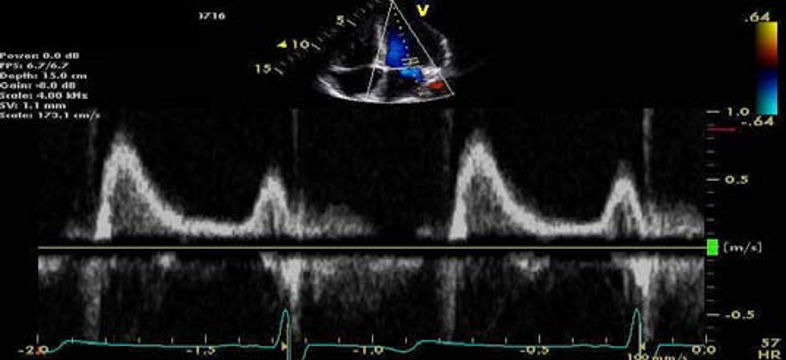

某患者二尖瓣血流频谱E峰测值80cm/s

同一患者,间隔侧二尖瓣环E/e'= 80/4 = 20

同一患者,侧壁二尖瓣环E/e'= 80/5 = 16